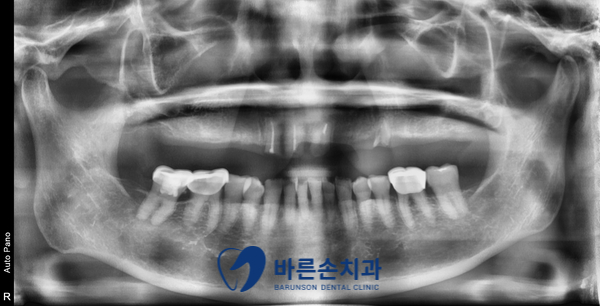

상악치아에 부분 틀니를 쓰시다가

틀니를 걸어서 쓰는 치아들이 부러진 환자분 입니다.

치아 뿌리만 남아 있고, 더 이상 기존 틀니를 사용할 수 없습니다.ㅠㅠ